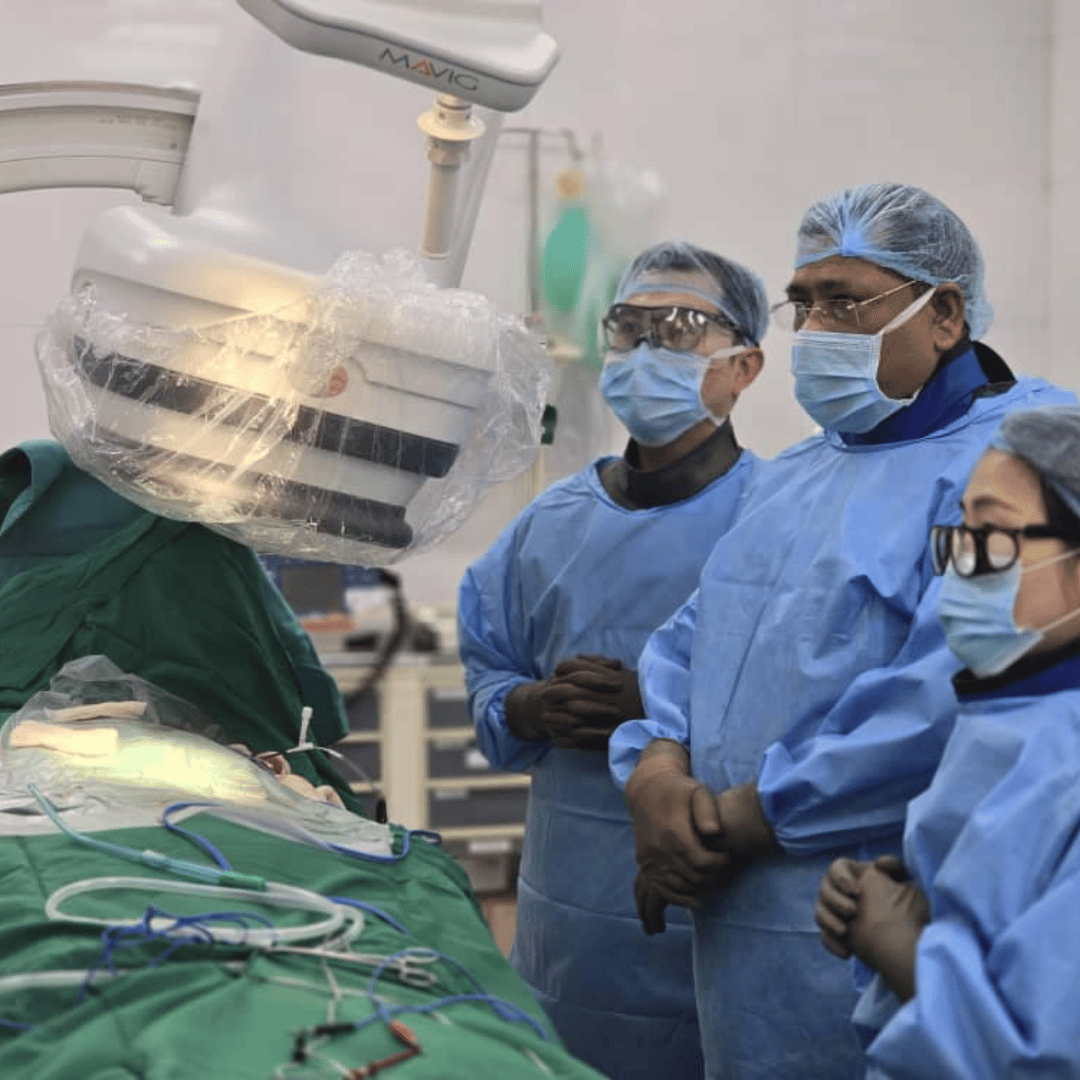

Mentoring young colleagues in their careers is truly rewarding. It was a pleasure to have enthusiastic young operators at our Medica CSP workshop. Additionally, I thoroughly enjoyed scrubbing with Dr. Mahesh at JDWNR Hospital in Thimphu, Bhutan.

CSP workshop at Bankura medical college. It was a great interaction with a highly enthusiastic and skilled team here .

"A Milestone in Cardiology: Successful CSP and CRT-D Procedures at JDWNRH"

"Successful Day of Complex Cardiac Interventions at Ebenezer Medical Center, Aizawl"

"A Thrilling Day of Advanced Cardiac Interventions with Dr. Sanjog Kalra and Team"